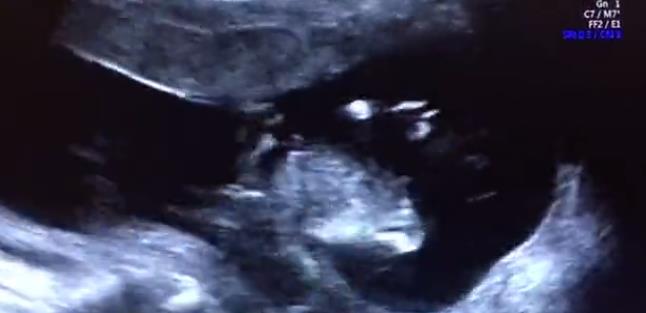

最后,我们再和大家分享两段

我院四维筛查双胞胎超声影像

两段筛查视频都是超声科孙辉医生

通过E10四维设备为双胎宝妈进行的

其中一位是不孕科治疗后迎来好孕

而另一位则是产科的产检分娩客户